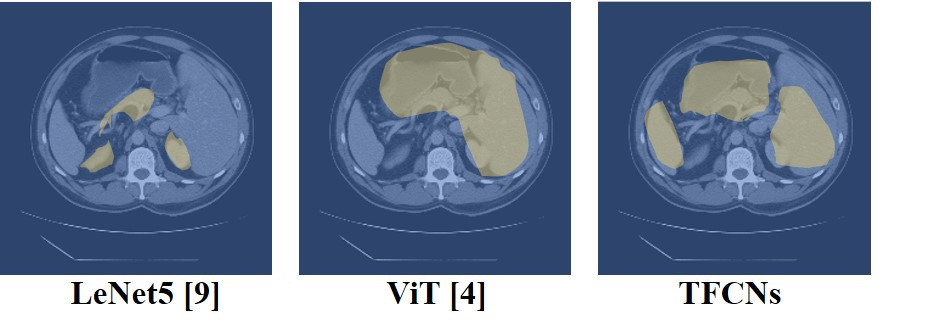

Medical image segmentation is one of the most fundamental tasks concerning medical information analysis. Various solutions have been proposed so far, including many deep learning-based techniques, such as U-Net, FC-DenseNet, etc. However, high-precision medical image segmentation remains a highly challenging task due to the existence of inherent magnification and distortion in medical images as well as the presence of lesions with similar density to normal tissues. In this paper, we propose TFCNs (Transformers for Fully Convolutional denseNets) to tackle the problem by introducing ResLinear-Transformer (RL-Transformer) and Convolutional Linear Attention Block (CLAB) to FC-DenseNet. TFCNs is not only able to utilize more latent information from the CT images for feature extraction, but also can capture and disseminate semantic features and filter non-semantic features more effectively through the CLAB module. Our experimental results show that TFCNs can achieve state-of-the-art performance with dice scores of 83.72\% on the Synapse dataset. In addition, we evaluate the robustness of TFCNs for lesion area effects on the COVID-19 public datasets. The Python code will be made publicly available on https://github.com/HUANGLIZI/TFCNs.